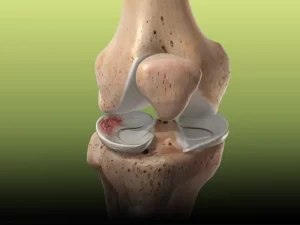

امروزه هزینه جراحی مینیسک زانو یکی از دغدغه های اصلی افراد است. بهتر است بدانید این جراحی به منظور ترمیم یا برداشتن بخش آسیب دیده

امروزه هزینه جراحی مینیسک زانو یکی از دغدغه های اصلی افراد است. بهتر است بدانید این جراحی به منظور ترمیم یا برداشتن بخش آسیب دیده

درمان پارگی مینیسک زانو یکی از موضوعات مهم در حوزه ارتوپد بوده که به دلیل تاثیر مستقیم آن بر حرکت و عملکرد زانو، توجه بسیاری

آرتروسکوپی زانو یکی از روشهای پیشرفته و کم تهاجم بوده که پزشکان با این روش مشکلات زانو را با دقت بالا تشخیص داده و این

آرتروسکوپی زانو یکی از پیشرفته ترین روشهای جراحی برای درمان مشکلات زانو بوده و دارای مزایای متعددی بوده به همین دلیل مورد توجه افراد قرار

پارگی رباط صلیبی زانو یکی از شایع ترین آسیب دیدگی زانو بوده که معمولا در هنگام فعالیت های فیزیکی مانند فوتبال، والیبال و اسکی بوجود